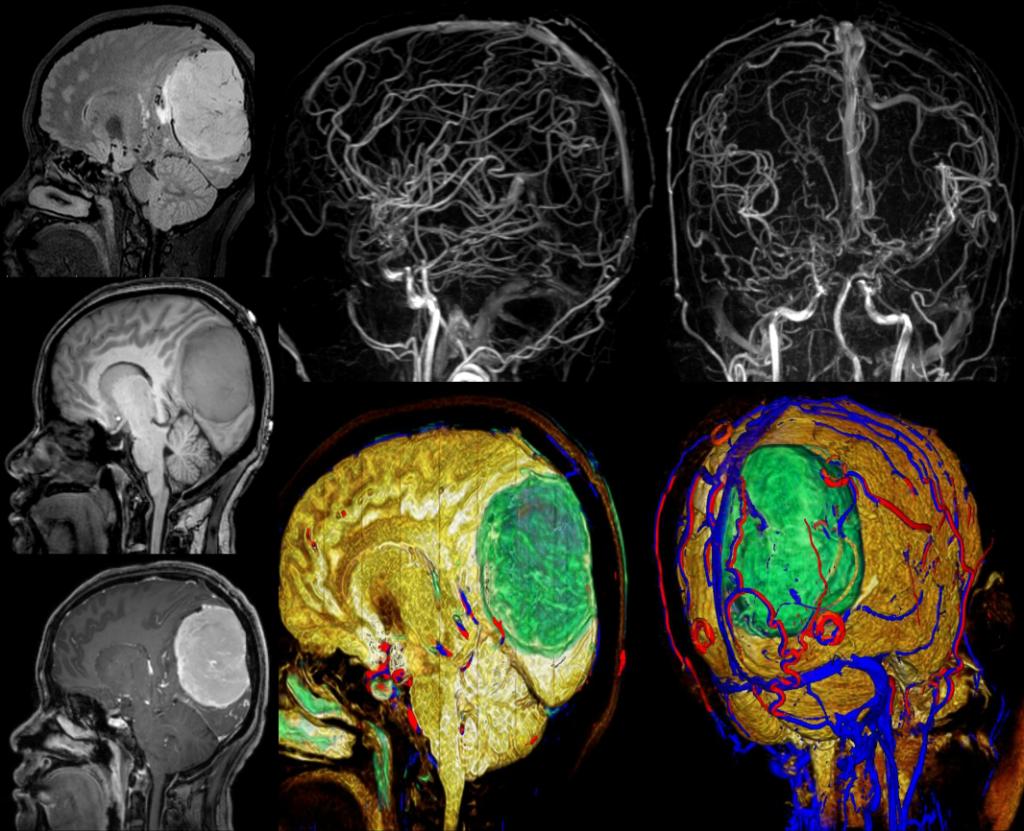

高分辨脑神经系统3D FLAIR成像技术显示局灶性皮质结构发育不良 高分辨脑神经系统mult-shot DWI 与传统single-shot成像技术对比,在脑灰质异位与急性脑皮质梗塞显示中更具优势。 3D SNAP-MRA 显示左大脑中动脉血管中断,3D FLAIR显示左脑萎缩及有功能的左手功能区,fMRI-Bold融合清晰显示功能区,DTI/FT 显示有功能的皮质纤维束。